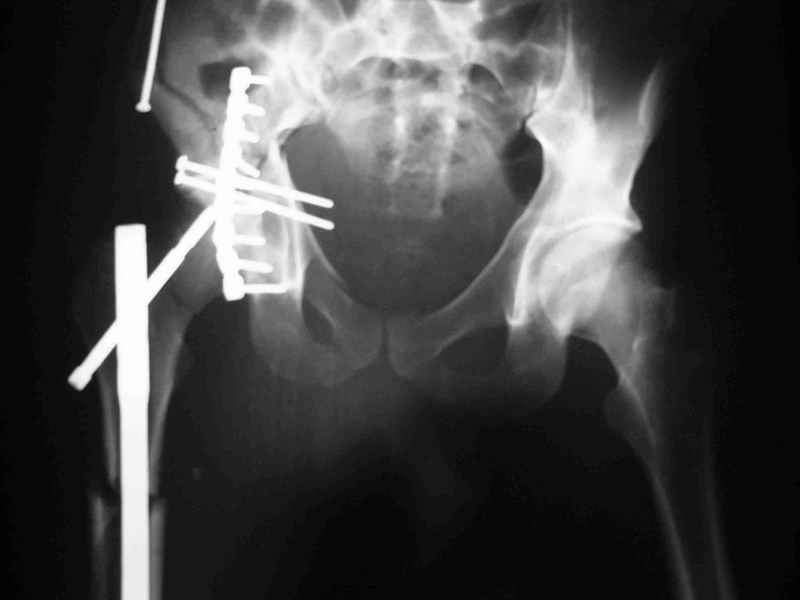

Уважаемые коллеги,Мужчина 36 лет от роду попал в ДТП 24.08.04 Рентгенограммы в приложении.

Диагноз- перелом с вовлечением таза, разрыв правого сакро-илиак сочленения vertical shear injury, перелом крыла подвздошной кости?, перелом ацетабулум Т type или Both column?, перелом шейки бедра, перелом проксимального отдела бедра.

перелом крыла правой подвздошной кости, перелом обеих колонн вертлужной впадины, двусторонний перелом лонных костей (С2.2) повреждение передних связок правого крестцово-подвздошного сочленения,

ипсилатеральный перелом шейки и диафиза бедра.